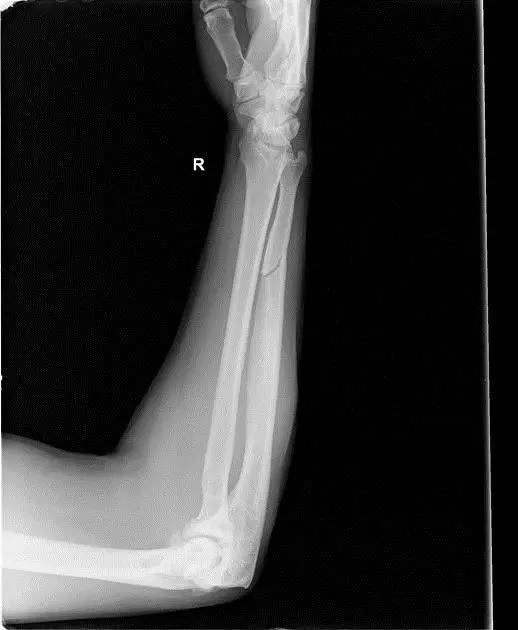

9. Monteggia 骨折(孟氏骨折)

尺骨近端 1/3 骨折合并桡骨头半脱位。

(来源:Radiopaedia)

成人 Monteggia 骨折

儿童 Monteggia 骨折